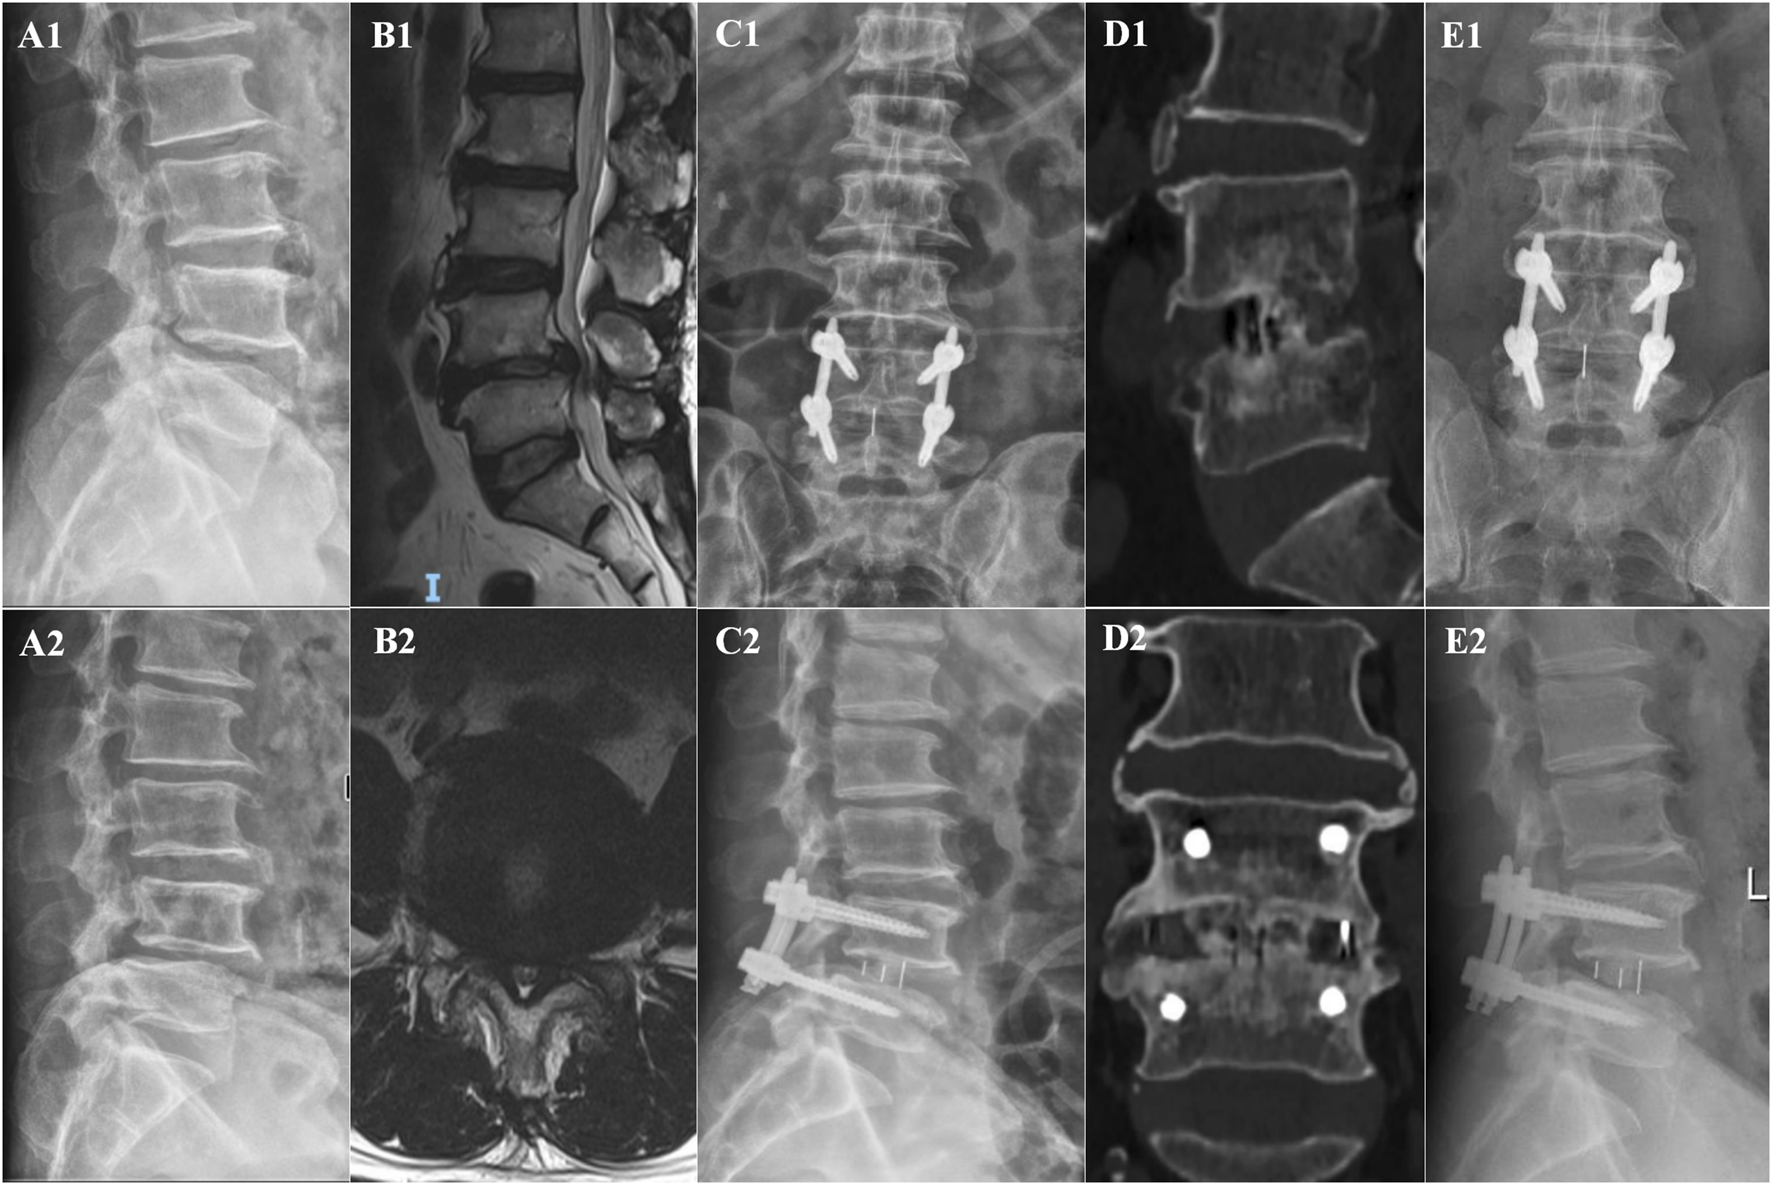

In the OLIF-BCAAS group, five cases (5/23, 21.74%) of CS were detected, with 4 out of 23 cases (17.39%) considered as mild CS. In contrast, the amount of CS was 12 cases (12/25, 48%) in the OLIF-PIFPS group, which included 3 cases of severe CS. There was a trend towards statistical difference in CS between the two groups (p = 0.057, Table 4). However, no significant differences were found in fusion rate at 6Â months and 12Â months postoperatively among the groups (p > 0.05, Table 4). Figures 2, 3 show the radiological images of the OLIF-BCAAS and OLIF-PIFPS typical cases.

FIGURE 3

The radiological images of OLIF-PIFPS typical case. (A1,A2) Preoperative dynamic X-ray films; (B1,B2) Preoperative sagittal and axial MR images; (C1,C2) A−P, lateral X-ray film at 1 day postoperatively; (D1,D2) Sagittal and coronal CT images at 12 months postoperatively; (E1,E2) A−P, lateral X-ray film at 12 months postoperatively.